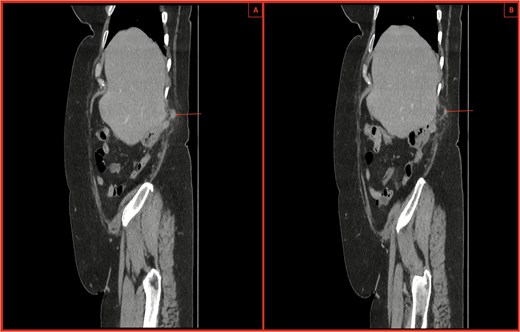

An urgent computed tomography (CT)-abdomen/pelvis highlighted an inflamed appendix extending into a small hernial defect in the right posterolateral abdominal wall (Figs 1–3). Thus, diagnosing retroperitoneal acute appendicitis within a right nephrectomy incisional hernia. The patient was started on intravenous Ceftriaxone and Metronidazole prior to deciding upon an open appendicectomy and repair of the incisional hernia using biological mesh.

(A, B) CT sagittal sections with notable posterior abdominal wall hernial defect and appendix within hernia highlighted by arrows. There is also notable inflammatory fat stranding, with no evidence of perforation.